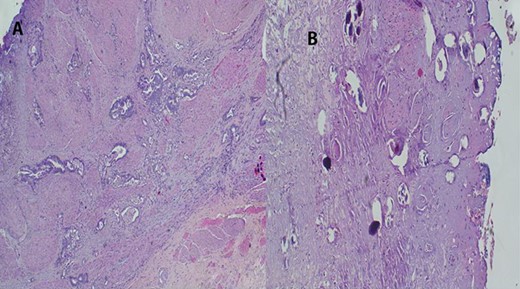

Urethrocystoscopy found to have extensive sand patch lesion in the urinary bladder with solitary solid tumor on the right side of the bladder wall extending from 3 to 5 o’clock. A transurethral resection of bladder tumor biopsy (TURBx) was done, and histological findings confirmed adenocarcinoma of the bladder with numerous calcified submucosal Schistosoma eggs (Fig. 7).

(A) Histopathology of urinary bladder with invasive adenocarcinoma, not otherwise specified (NOS), H&E ×10 magnification. (B) Schistosoma ova near or within the tumor, ×4 magnification.